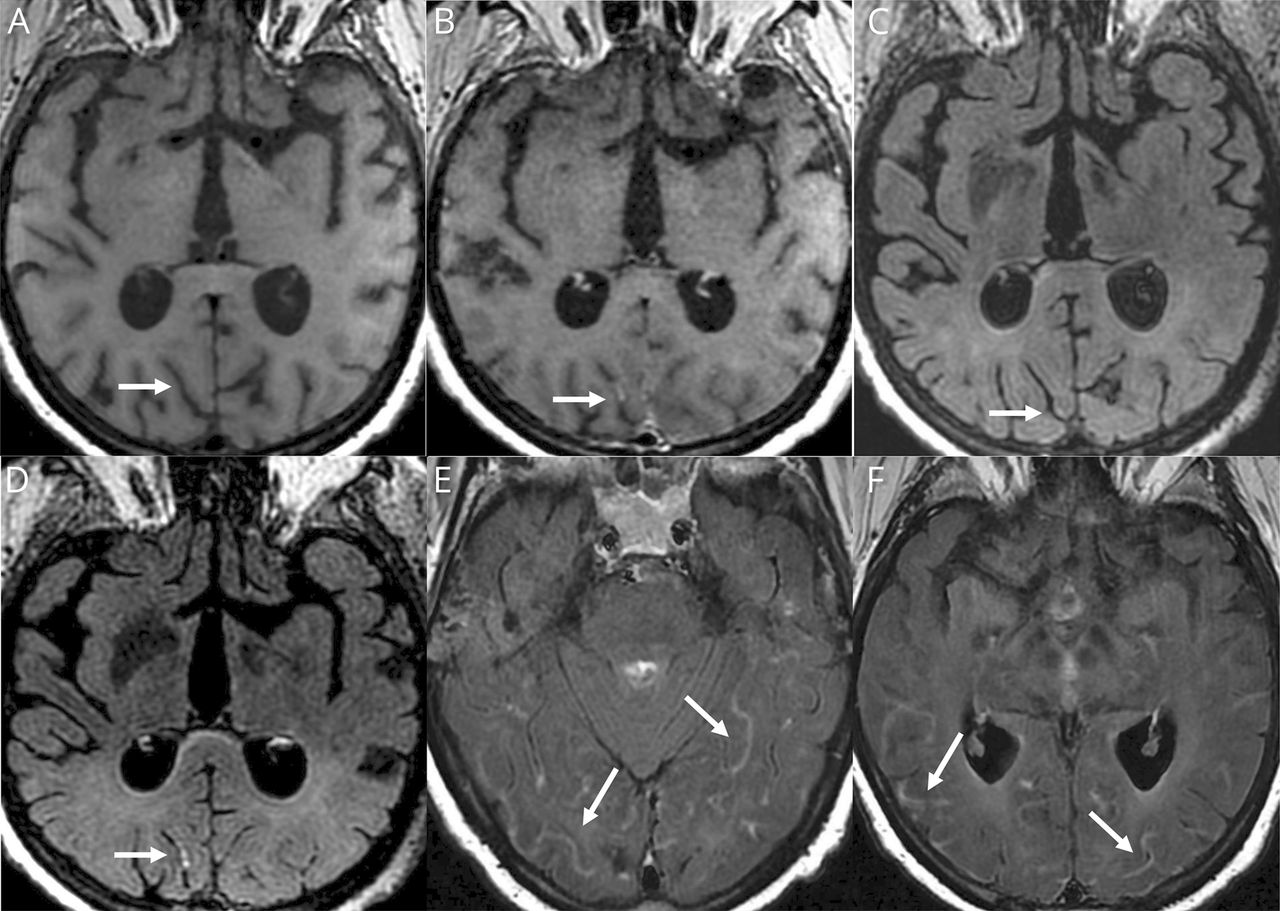

Ischemic strokes (27%) (figure e-1, available from Dryad,doi.org/10.5061/dryad.w9ghx3fm7), LME (17%) (figure 1), and encephalitis (13%) (figures 2and3and figure e-2, available from Dryad) were the most frequent neuroimaging findings. LME was seen on both postcontrast T1-weighted and FLAIR sequences and was even better visualized when delayed postcontrast FLAIR was performed. These signal abnormalities were not present on precontrast T1 or FLAIR images.

Axial T1 (A) before and (B) 5 minutes after contrast, axial FLAIR (C) before and (D) immediately after contrast, and (E and F) delayed (10 minutes) postcontrast axial fluid-attenuated inversion recovery (FLAIR) weighted MRIs. Woman 77 years of age: diffuse leptomeningeal linear FLAIR and T1 contrast enhancement (arrows) not visible on precontrast T1 and FLAIR (arrows) but seen better on delayed postcontrast FLAIR weighted MRIs (E and F).